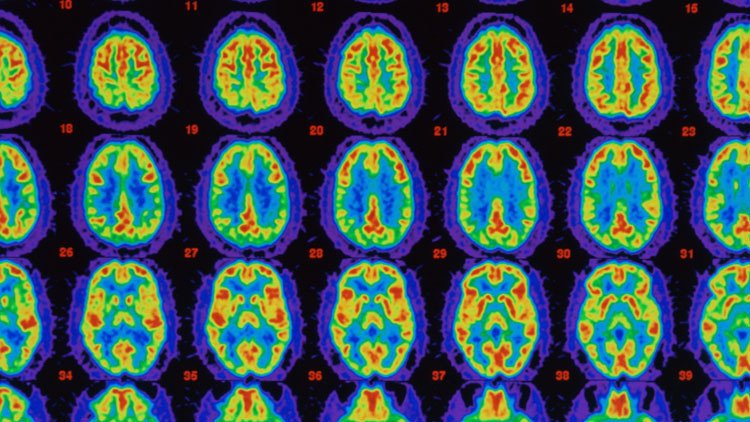

El doctor Doug Brown explicó durante la conferencia cómo el medicamento reduce las placas de proteína beta-amiloide que se acumulan en el cerebro, retardando el proceso degenerativo de la enfermedad.